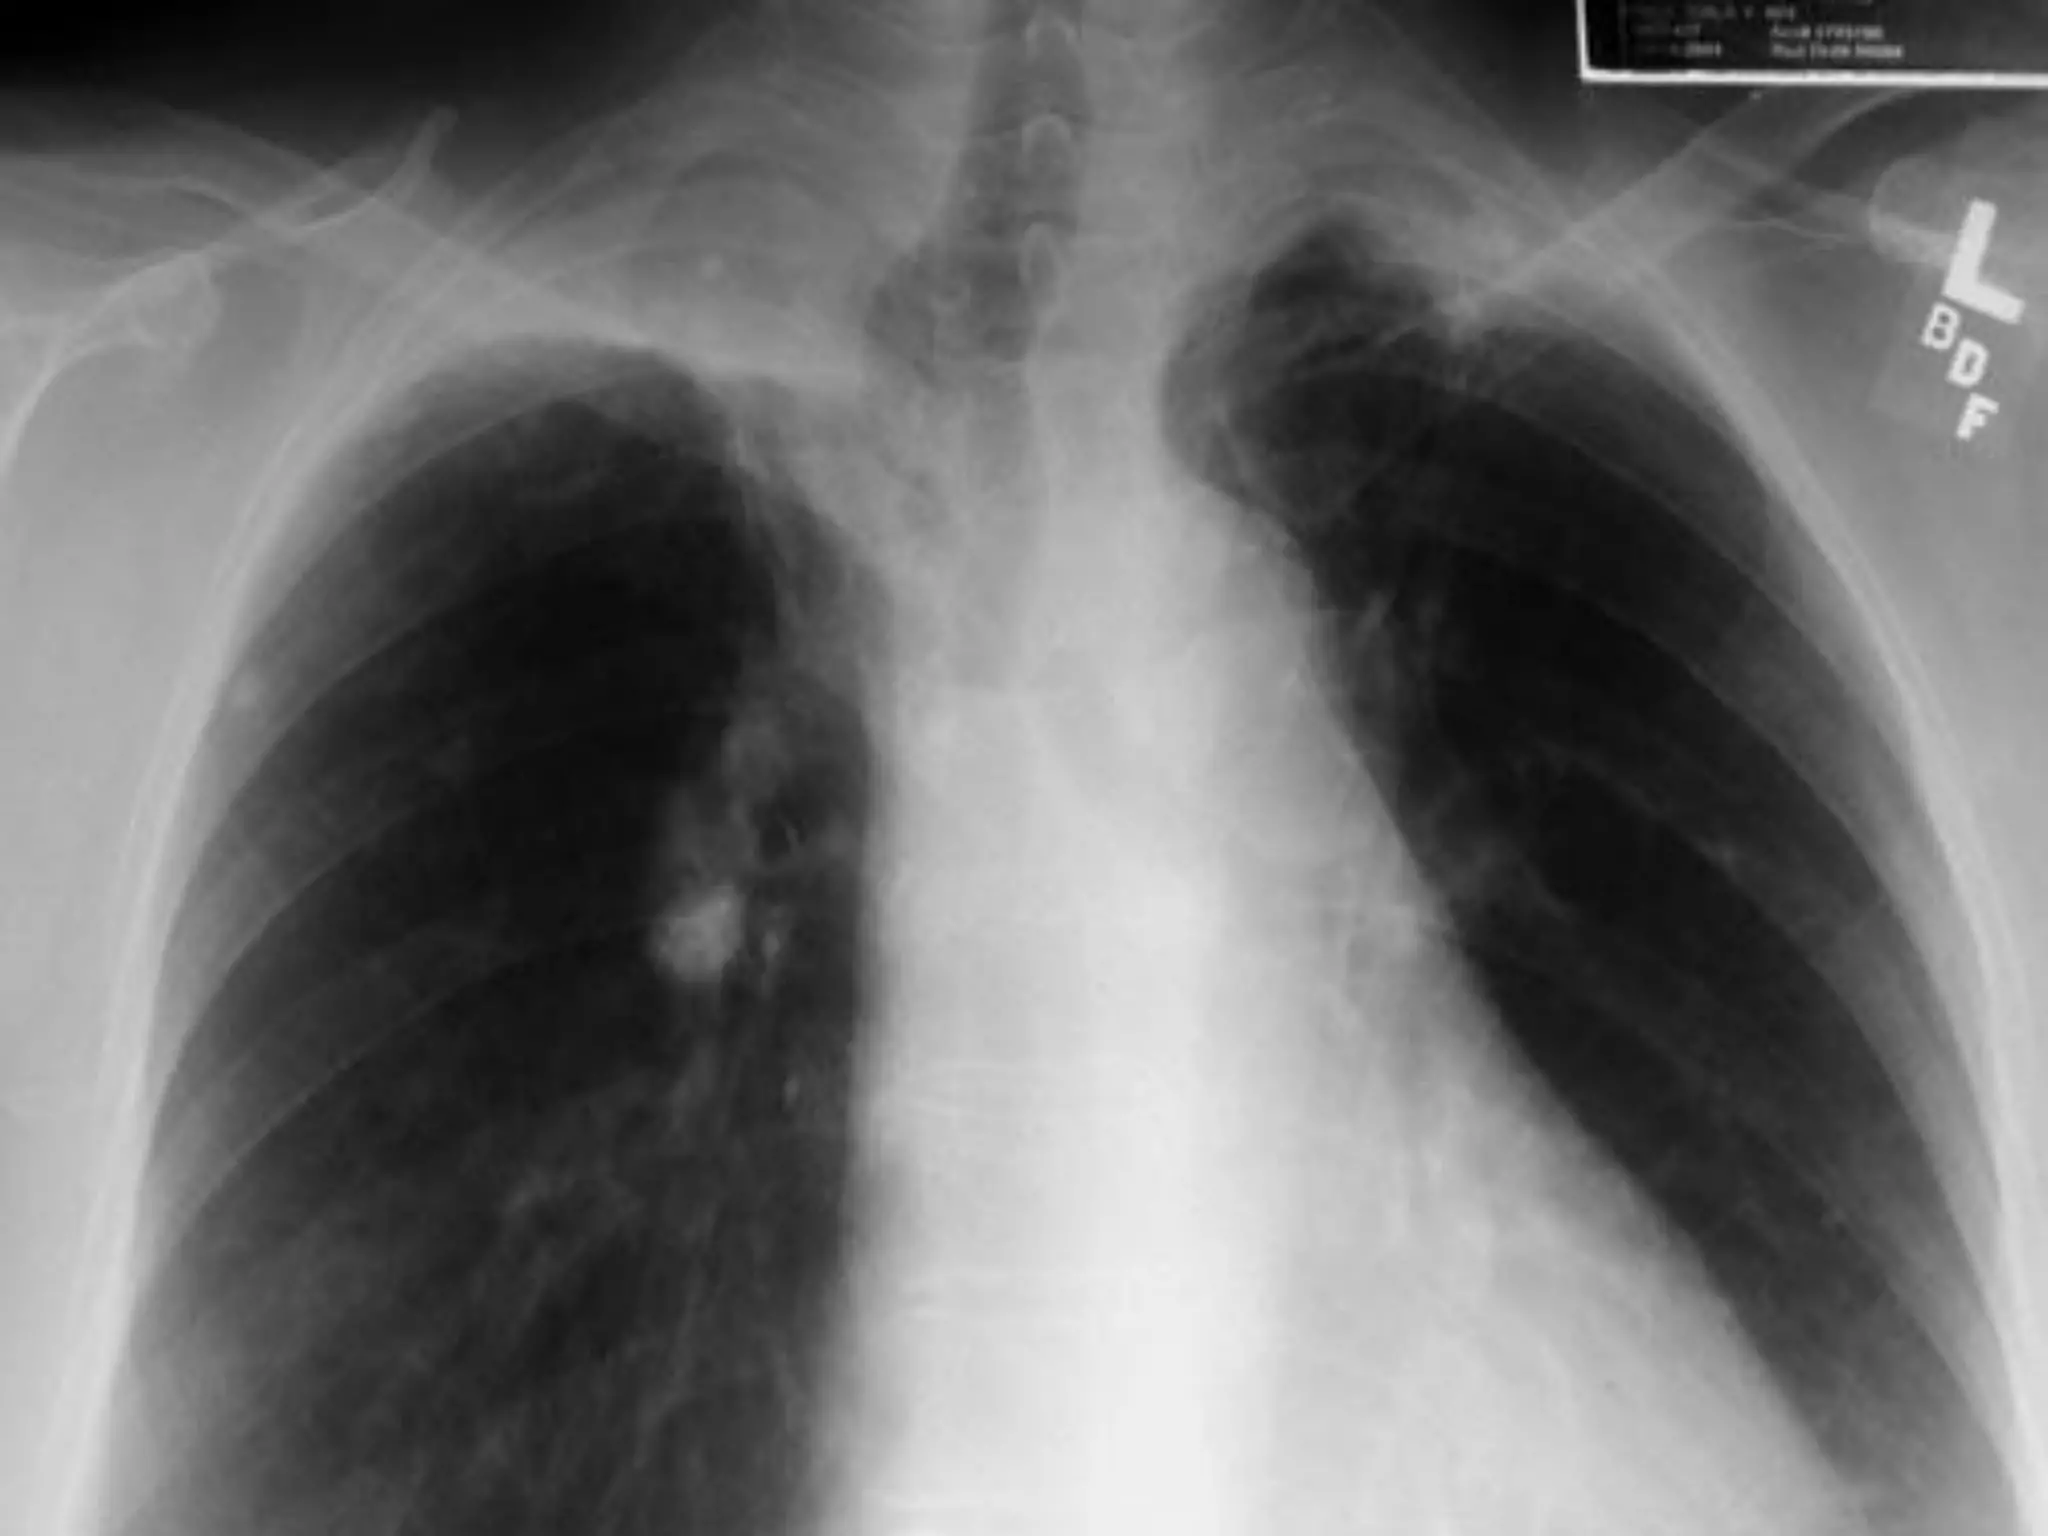

CXR Findings

Primary TB:



Reactivated TB:

Lower or middle lobe infiltrates

Apical infiltrates/cavitation

Latent TB:

Usually normal

 Nodules in hilar area or upper lobes

 Pleural scarring/thickening